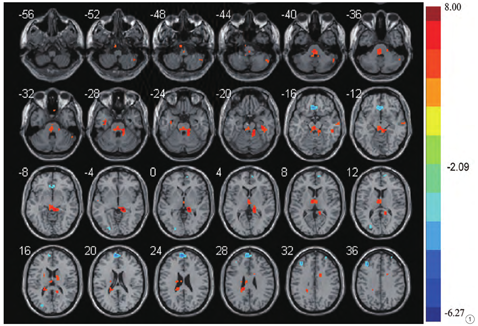

患者组与对照组局部一致性差异脑区见图1。

患者组双侧梭状回、双侧扣带回及右侧小脑脚2区、右侧丘脑、右侧颞中回及左侧丘脑内侧背核等脑区的ReHo显著高于对照组(P<0.05FDR校正,cluster size>10)。见表1。

患者组双侧内侧额上回及左侧额中回、左侧额内侧回、左侧枕中回、左侧枕下回及左侧中央旁小叶等脑区ReHo显著减低(P<0.05FDR校正,cluster size>10)。见表2。